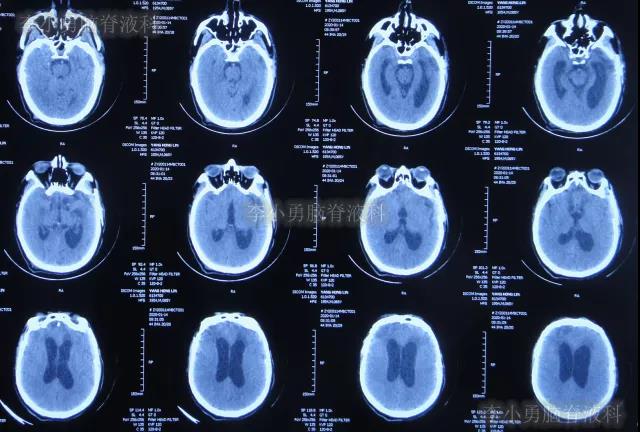

在第4家医院治疗26天,仍间断性发热、大小便失禁加重,住院期间曾2次查头颅CT(2020年2月27日(图-28)、2020年3月12日(图-29))示脑室仍扩张。

图-28:2020年2月27日头颅CT

图-29:2020年3月12日头颅CT

2020年3月18日(颅脑外伤开颅术后149天即颅骨修补术后95天即第2次脑室腹腔分流术后62天,先后经4家医院治疗后仍意识模糊,大小便失禁,脑积水,间断发热近2月)转住入李小勇脑脊液科。入院时:意识模糊,大小便失禁,体重较前明显减轻,体温高38度左右;头部可见引流管走向;右侧肢体活动差些;鼻饲流食(图-30);入院时头颅CT示颅骨修补术后、脑室引流术后仍脑积水,有水肿(图-31)。

图-31:2020年3月18日头颅CT